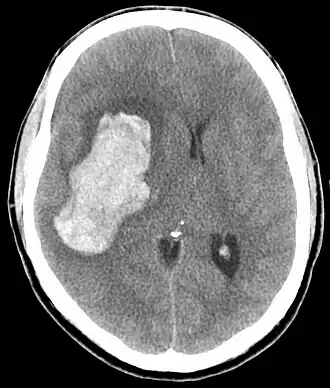

| TC de uma hemorragia intracraniana, uma possível complicação de uma emergência hipertensiva. | |